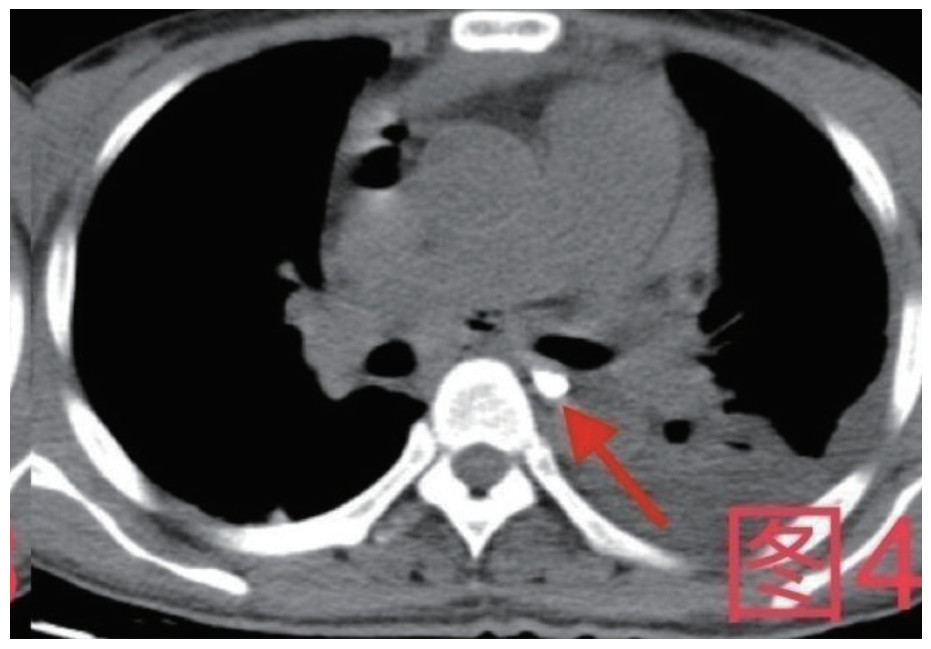

治疗经过:急诊予美罗培南0.5 g,1次/12 h抗感染,补液支持,心包引流等治疗措施,收住感染科后继续抗感染治疗,期间心包积液培养出白假丝酵母菌,加用氟康唑200 mg,1次/d, 口服,心包积液、左侧胸腔积液引流等措施,治疗10 d后复查胸部CT仍有中大量心包积液伴少许积气,纵隔积气;左侧少量胸腔积液,两肺叶间裂少许积液。对照前片(2020.10.26)心包积气及左侧胸前积液有增多,叶间裂积液新发,心包积液略有减少。右肺下叶感染,左肺下叶膨胀不全,较前右肺下叶感染有吸收,左肺下叶膨胀不全新发。考虑不能排除食管纵隔瘘,予口服碘海醇后胸部CT检查(图 3~6):约胸6椎体水平食管纵隔瘘,瘘口为相应水平食管壁右前方可能;胃镜(图 7):食道距门齿25 cm右后壁见一直径约1.0 cm凹陷,内有一小瘘口。胃镜下予钛夹2枚夹闭瘘口(图 8),同时植入空肠营养管。至此患者病情明确诊断食管心包瘘,患者经以上治疗后心包积液、胸腔积液逐渐减少,于11月13日拔除心包及胸腔引流管,因患者签字回当地就诊,予口服莫西沙星、氟康唑带药出院,出院后随访,患者未回当地医院治疗,仅在家中继续空肠营养管饲喂及口服抗菌药物治疗。

| 图 4 患者卧位第一次口服15 mL碘海醇后,箭头所指为食管内碘海醇,未见食管内碘海醇漏出 |